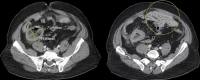

Meckel's diverticulum (MD) is one of the most common congenital abnormalities of the gastrointestinal tract, affecting approximately two percent of the population. Rarely, Meckel's diverticula have been found to harbor various tumors, which go unnoticed until later in their course. The clinical presentation varies among each individual, and tumors have often metastasized or caused diverticular rupture at the time of diagnosis. This is a case of a 55-year-old male with a past medical history of alcohol abuse and asthma who presented to the emergency department with abdominal pain. He denied any fever, chills, chest pain, nausea, changes in urinary patterns, recent travel, or sick contacts. He is a non-smoker but has been a heavy drinker for many years. On physical exam, he was found to have diffuse abdominal tenderness with pain greatest in the epigastric region and no bowel sounds. He was afebrile but tachycardic at 112 bpm, hypertensive at 168/98 mmHg, and tachypneic at 38 bpm. Labs showed a markedly elevated white blood cell count, hemoglobin and platelet count, as well as metabolic acidosis and elevated lactate levels. Abdominal CT showed a mechanical small bowel obstruction with unclear etiology. Of note was a 7.2 cm thick-walled collection in the right lower quadrant having no clear communication with any bowel loops. Despite aggressive hydration and supportive care, his abdominal exam continued to worsen, prompting an exploratory laparotomy. During the laparotomy, a perforated MD with frank succus was found. On pathology, the affected segment of the bowel revealed a CD117 and CD34 positive spindle cell gastrointestinal stromal tumor (GIST) with mild cytological atypia, no necrosis, and no regional lymph node involvement. Cultures of peritoneal fluid were positive for Klebsiella oxytoca, and the patient was started on meropenem and doxycycline. The patient showed significant improvement with the appropriate administration of antibiotics and was eventually discharged to follow-up with hematology/oncology as an outpatient for further management and monitoring of his GIST tumor. This case is unique as there are only a few reported cases of patients developing GIST inside of MDs. Despite the high five-year survival rate of typically localized GIST tumors, the complications (such as perforation in the case of our patient) caused by tumor growth inside a MD are detrimental if not diagnosed promptly. Not only does perforation increase the risk of metastasis but also the risk of peritonitis and other complications. This case calls for more research on standardization of care for patients who have MD to prevent malignant transformations as well as potential prophylactic excision of incidental MD findings in adult patients.